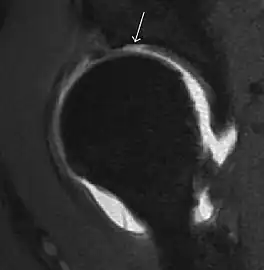

Most of the angles and measurements described in the plain radiograph section can be accurately reproduced on MRI. In addition, the superiority of MRI resolution with intra-articular contrast allows detection of labral and chondral abnormalities that may influence the choice of medical, percutaneous, or surgical management (Figure 9).[1]

Figure 9:

-

Sagittal T1 weighted image showing anterosuperior labral tear.[1] -

Sagittal T1 weighted image showing chondral lesion.[1] -

Sagittal CT-arthrography showing posteroinferior chondral injury.[1] -

Coronal CT-arthrography (d) showing ligamentum teres tear.[1]

MR arthrography has proven superior in accuracy when compared to native MR imaging. It is considered the best technique to assess the labrum. Knowledge of the normal variable morphology of the labrum helps to differentiate tears from normal variants. A triangular shape is most commonly seen in 66% of asymptomatic volunteers, but round, flattened, and absent labra can also be found in asymptomatic populations. MR arthrography has demonstrated sensitivity over 90% and specificity close to 100% in detecting labral tears. Loose bodies are demonstrated as filling defects surrounded by the hyperintense gadolinium.[1]

Association between labral tears and chondral damage has been demonstrated. This underscores the interaction between cartilage and labrum damage in the progression of osteoarthritis. Chondral damage to the posteroinferior part of the acetabulum as a contrecoup lesion occurs in approximately one-third of pincer cases secondary to persistent abutment on the anterior part of the joint leading to a slight posteroinferior subluxation. This is considered a bad prognosis sign.[1]

MR arthrography can also demonstrate ligamentum teres rupture or capsular laxity, which are debated causes of microinstability of the hip. Elongation of the capsule or injury to the iliofemoral ligament or labrum may be secondary to microtrauma in athletes. MR can demonstrate abnormalities in these cases, such as increased joint volume or a ligamentum teres tear (Figure 9).[1]